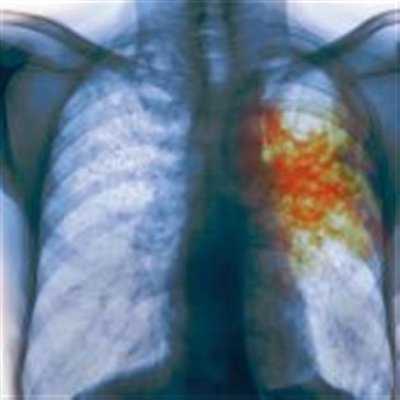

- Инфильтративный туберкулез выражается в скоплении большого количества клеточных элементов с кровяной примесью. Скопившийся инфильтрат в лёгких частично выходит с кашлем в виде кровяной мокроты, что является опасным для окружающих.

- Кавернозная форма лёгочного поражения при туберкулёзе характерна рядом симптоматических признаков (кровохарканье, глухой хрип в лёгких). Поражение крупных сосудов лёгочной системы приводит к внутреннему кровотечению, что влечет за собой гнойные и кровянистые выделения при кашле.

Кровохарканье — признак развития инфильтративной формы туберкулеза. Наблюдается отхождение мокроты с частицами крови. Это опасное явление, поскольку высока вероятность развития кровотечения в легких.

Туберкулез — замаскированная болезнь. Симптомы можно спутать с другими заболеваниями: рак легкого, сердечная недостаточность. Опасность представляет кровохарканье при туберкулезе с появлением приступообразного кашля, вылетом изо рта мокроты с частицами свежей крови. Развития легочного кровотечения — нередкая причина летального исхода.

На поздней стадии недуга мокрота может окрашиваться в алый оттенок. Это обусловлено тем, что сильный, изнуряющий кашель может спровоцировать постепенное разрушение капилляров, расположенных в районе легких.